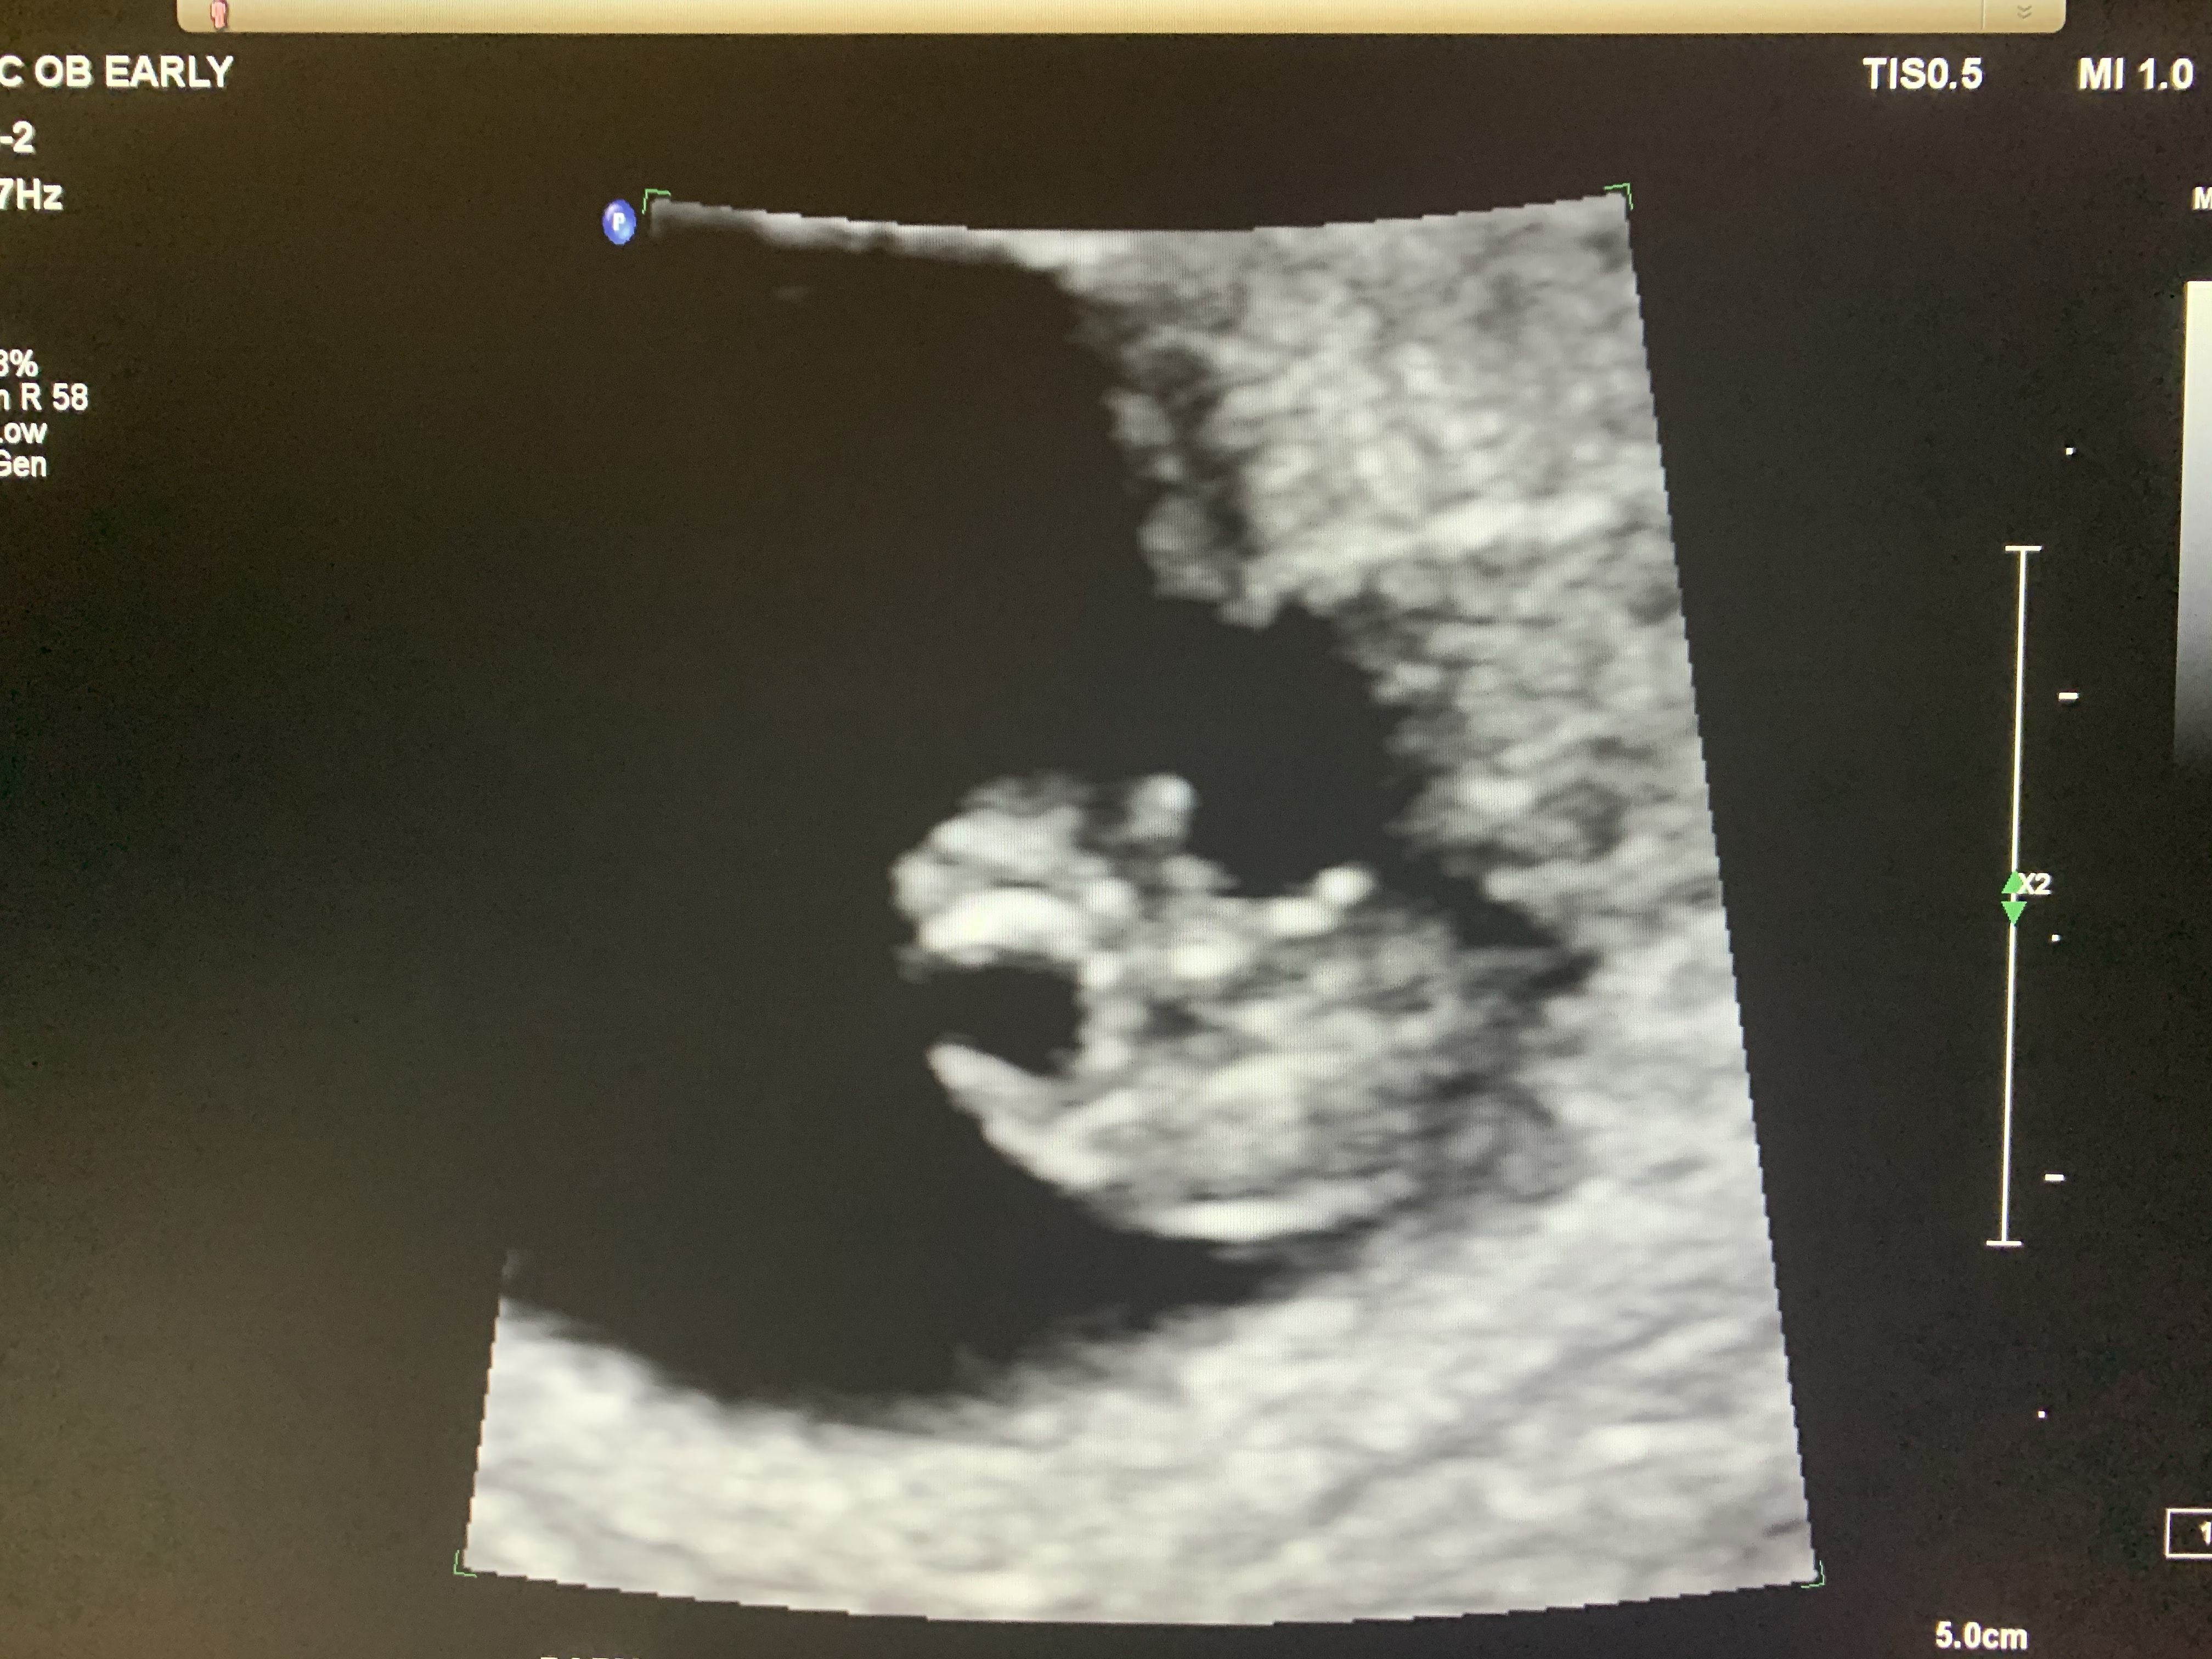

Coming home, I called again and got an appointment for early in the morning. When we got to the ultrasound clinic, I was in tears. I insisted to have Jeff with me in the room. The tech was very nice. Especially after we explained the situation to her a little bit. Within the first couple minutes, as my tears were running down my face, she turned to us and told us the sweetest words I have heard in the longest time “Heartbeat 122”.

At that point I broke down. Even just writing this I get teary-eyed. Somehow our miracle, was miraculously alive, growing and on track. The video I took of the strong heart beat, quickly became my favourite video to watch. I don’t even know how many times I watched it.